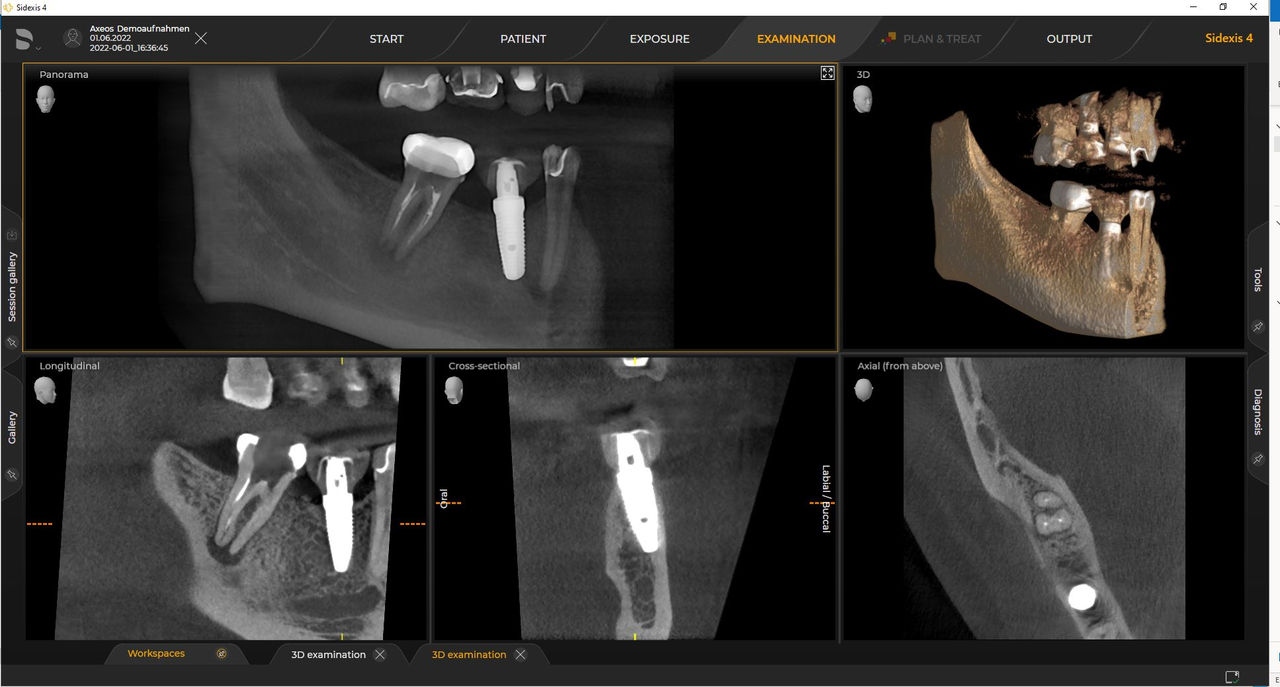

Los numerosos tamaños de volumen garantizan la flexibilidad en la práctica diaria. Examine un área precisa o evalúe la dentición completa, lo que incluye las ATM

Con el modo de dosis baja inteligente, obtiene radiografías 3D en el rango de dosis de una 2D. En el modo HD (hasta 1400), las imágenes individuales se obtienen durante una única rotación y se convierten en un volumen 3D con hasta 80 μm para imágenes de bajo ruido en alta resolución

Las unidades 3D de Dentsply Sirona funcionan exclusivamente con Sidexis 4. Sin embargo, la migración de datos de Sidexis XG a Sidexis 4 es muy fácil. Sidexis 4 permite una experiencia digital completa con las últimas herramientas.